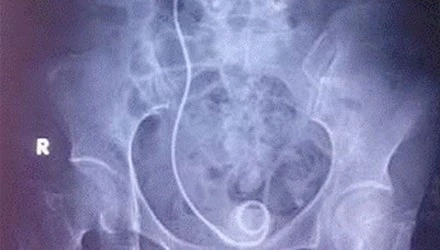

Ống thông JJ bỏ quên trong cơ thể người bệnh, bị gãy và bám sỏi 2 đầu.

Trong đó, thời gian bỏ quên “vật lạ” trung bình là 1,63 năm (có trường hợp bị bỏ quên ống này trong người suốt 8 năm), 9/24 trường hợp không biết sự tồn tại ống này trong cơ thể, 20/24 có sỏi bám ống thông, 8/14 bị nhiễm khuẩn đường tiết niệu, 6/24 biến chứng gãy ống thông… Dù các bác sĩ đã rút ống thông thành công nhưng có người bị choáng nhiễm trùng và đã tử vong.

Ống nhựa y khoa nằm trong người người bệnh hằng chục năm, bị bám sỏi, nhiễm trùng.